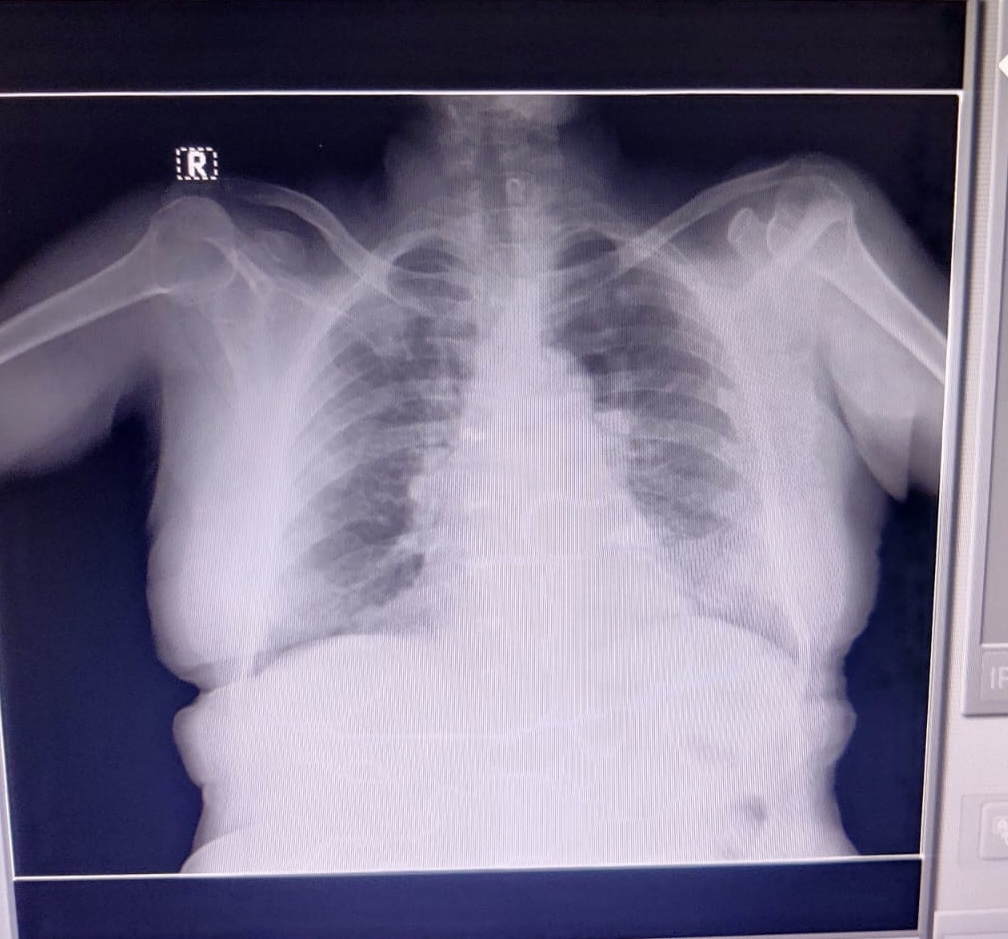

X-RAY

Pyrexia secondary to lower respiratory tract infection with h/o bronchial asthma (exacerbation)